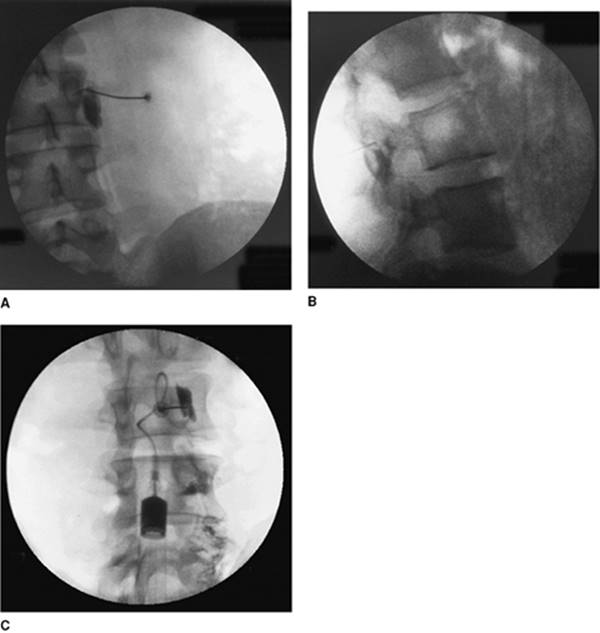

Approach and Technique: The lumbar region is prepared and draped using usual sterile techniques. Using fluoroscopy, the C-arm is positioned at 25° obliquely, using the minimum obliqueness that allows visualization of the eye of the Scotty dog. The tip of the needle is properly positioned by the use of multiplane fluoroscopic views. After confirming negative aspiration of CSF, contrast dye is injected to confirm position. This is then followed by the injection of the local anesthetic and steroid mixture. Figure 64-2 presents anteroposterior (A), lateral (B), and oblique views (C) with dye.

Figure 64-2. Anteroposterior (A), lateral (B), and oblique (C) views with dye.